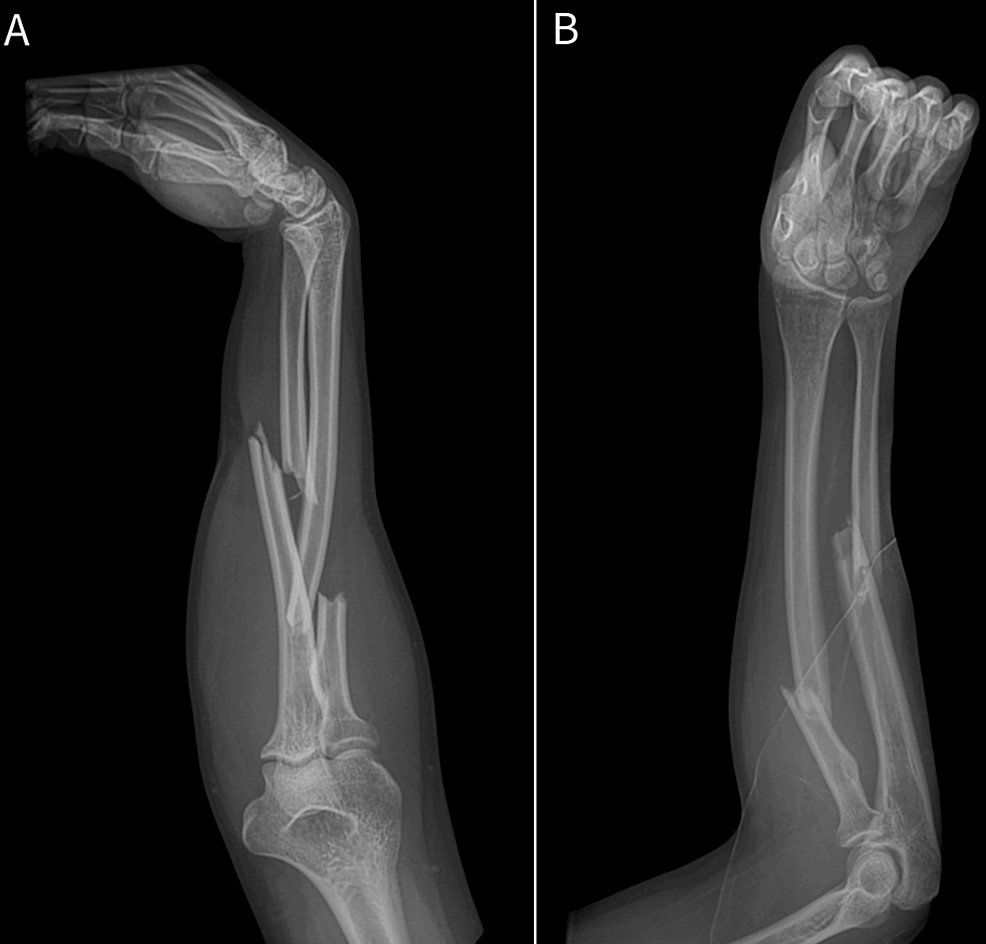

From litfl.com

ICE 001 Forearm injury • LITFL • ICE Clinical Cases Sore Forearm From Batting When you’re off the field nursing a sore arm, it’s crucial to determine the severity of your pain. When forearm pain is sudden and sharp, it may indicate an emergency that requires immediate medical attention. Forearm pain can affect the bones, muscles, and joints in the front part of your arm. Forearm tendonitis is inflammation of the tendons of the. Sore Forearm From Batting.

From www.cureus.com

Acute Compression of the Anterior Interosseous Nerve After a Proximal Sore Forearm From Batting Forearm tendonitis is inflammation of the tendons of the forearm. Treatment depends on the cause. The forearm is the part of your arm between the wrist and the elbow. However, applying warm or cool packs, taking pain relief. If your forearm is hurting you, it could be because your tendons are inflamed. Forearm pain can happen for many reasons, such. Sore Forearm From Batting.